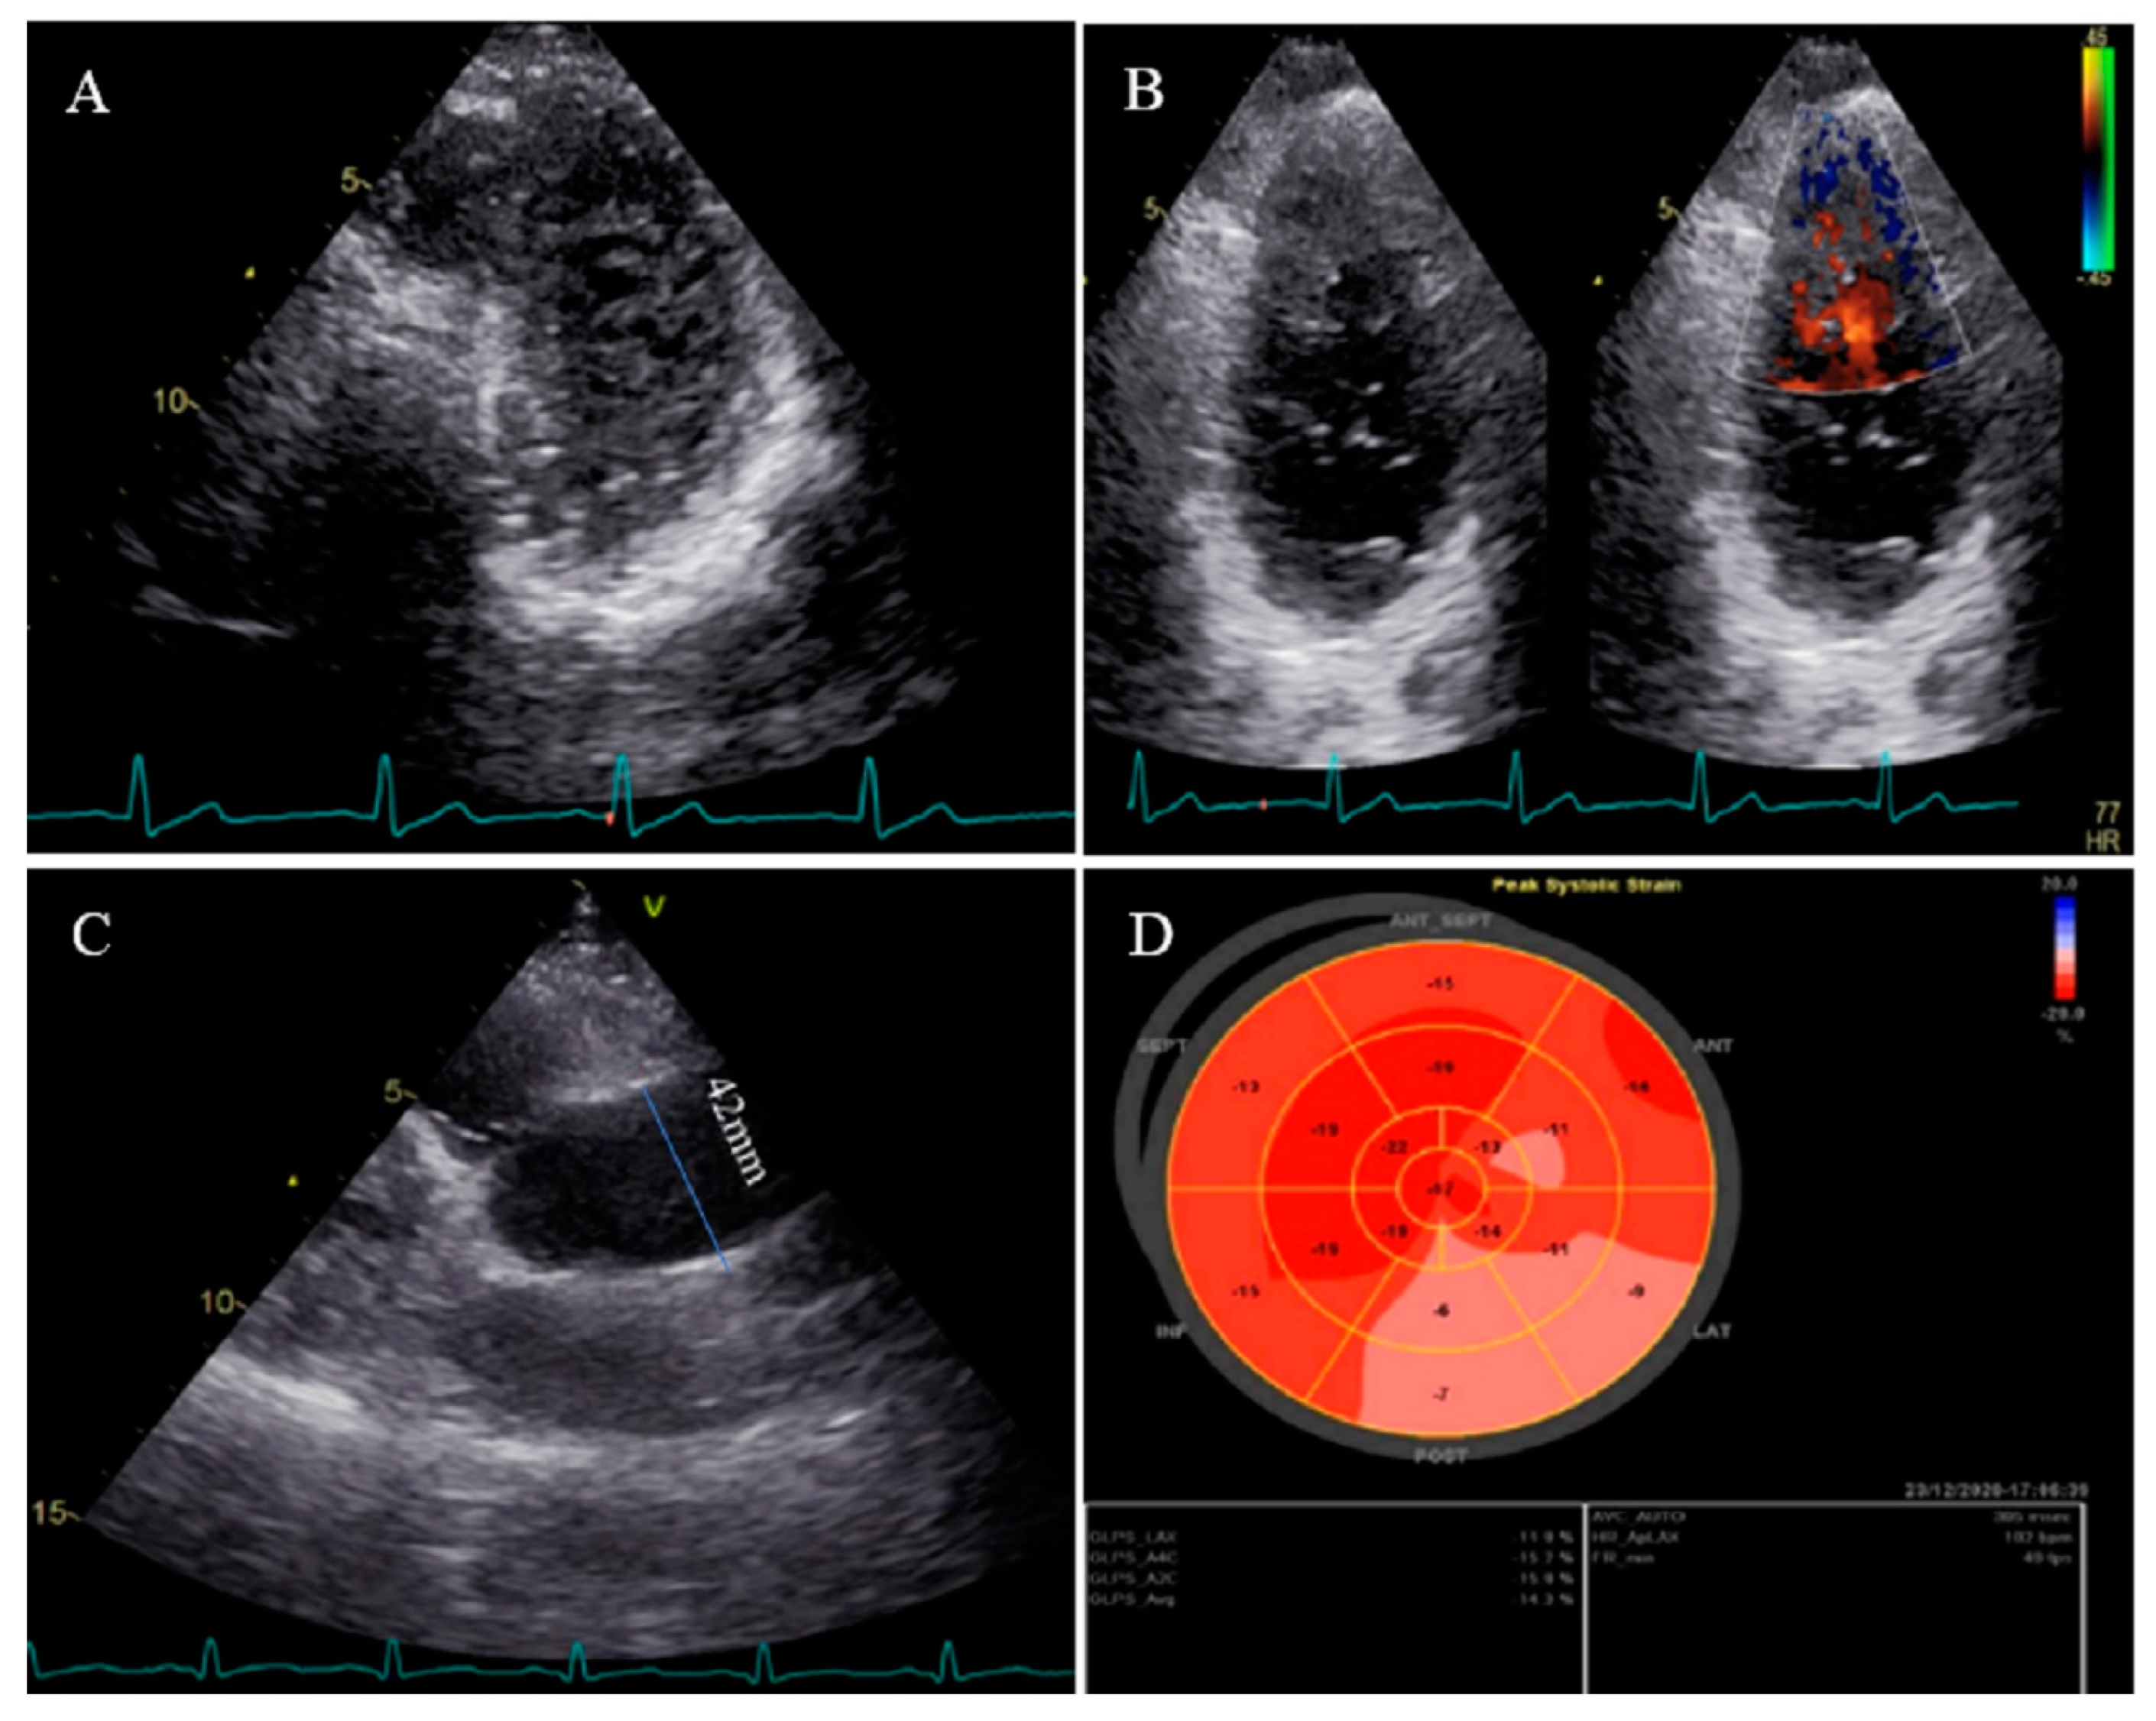

2.12. Case #12. BVNC with a Dilated Aorta

| 12 | M | 58 | History of palpitation and shortness of breath on heavy exercise | − | BVNC, LVEF = 55% | Dilated aorta | − | + | carvedilol; 6.25 mg BID | Doing well |